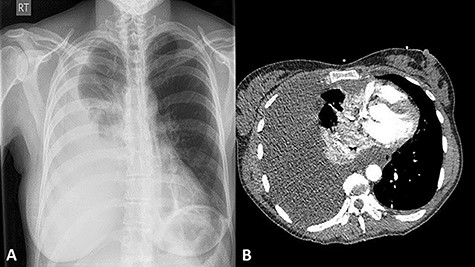

A 42-year-old female presented to the Accident and Emergency department with worsening dyspnoea. This was precipitated by a 6 ft fall from a bucked horse 1 week prior to presentation, in which, she sustained injuries to her back. Her vital observations were within the normal range and the pulse oximetry oxygen saturation was 100% on room air. There were decreased breath sounds on the auscultation of her right lung base and some minor bruising noted over the mid-thoracic spine area. A plain chest X-ray (CXR) (Fig. 1A) showed a right sided pleural effusion. A contrast-enhanced computed tomography (CT) scan of her thorax (Fig. 1B) revealed a large effusion with low Hounsfield Units and consistent with non-haemorrhagic material. There was a noted absence of rib fractures, but it did show a single non-displaced fracture of the T10 spinous process. Vigilance was maintained given the difficulty in detecting even minor bony injuries on cross-sectional imaging allied with the mechanism of injury.

A postero-anterior plain CXR showing a large right-sided pleural effusion (A); a contrast-enhanced CT scan showing large right-sided pleural effusion causing right lung collapse and left mediastinal shift with compression of the right atrium; note the intact ribs and vertebra (B).